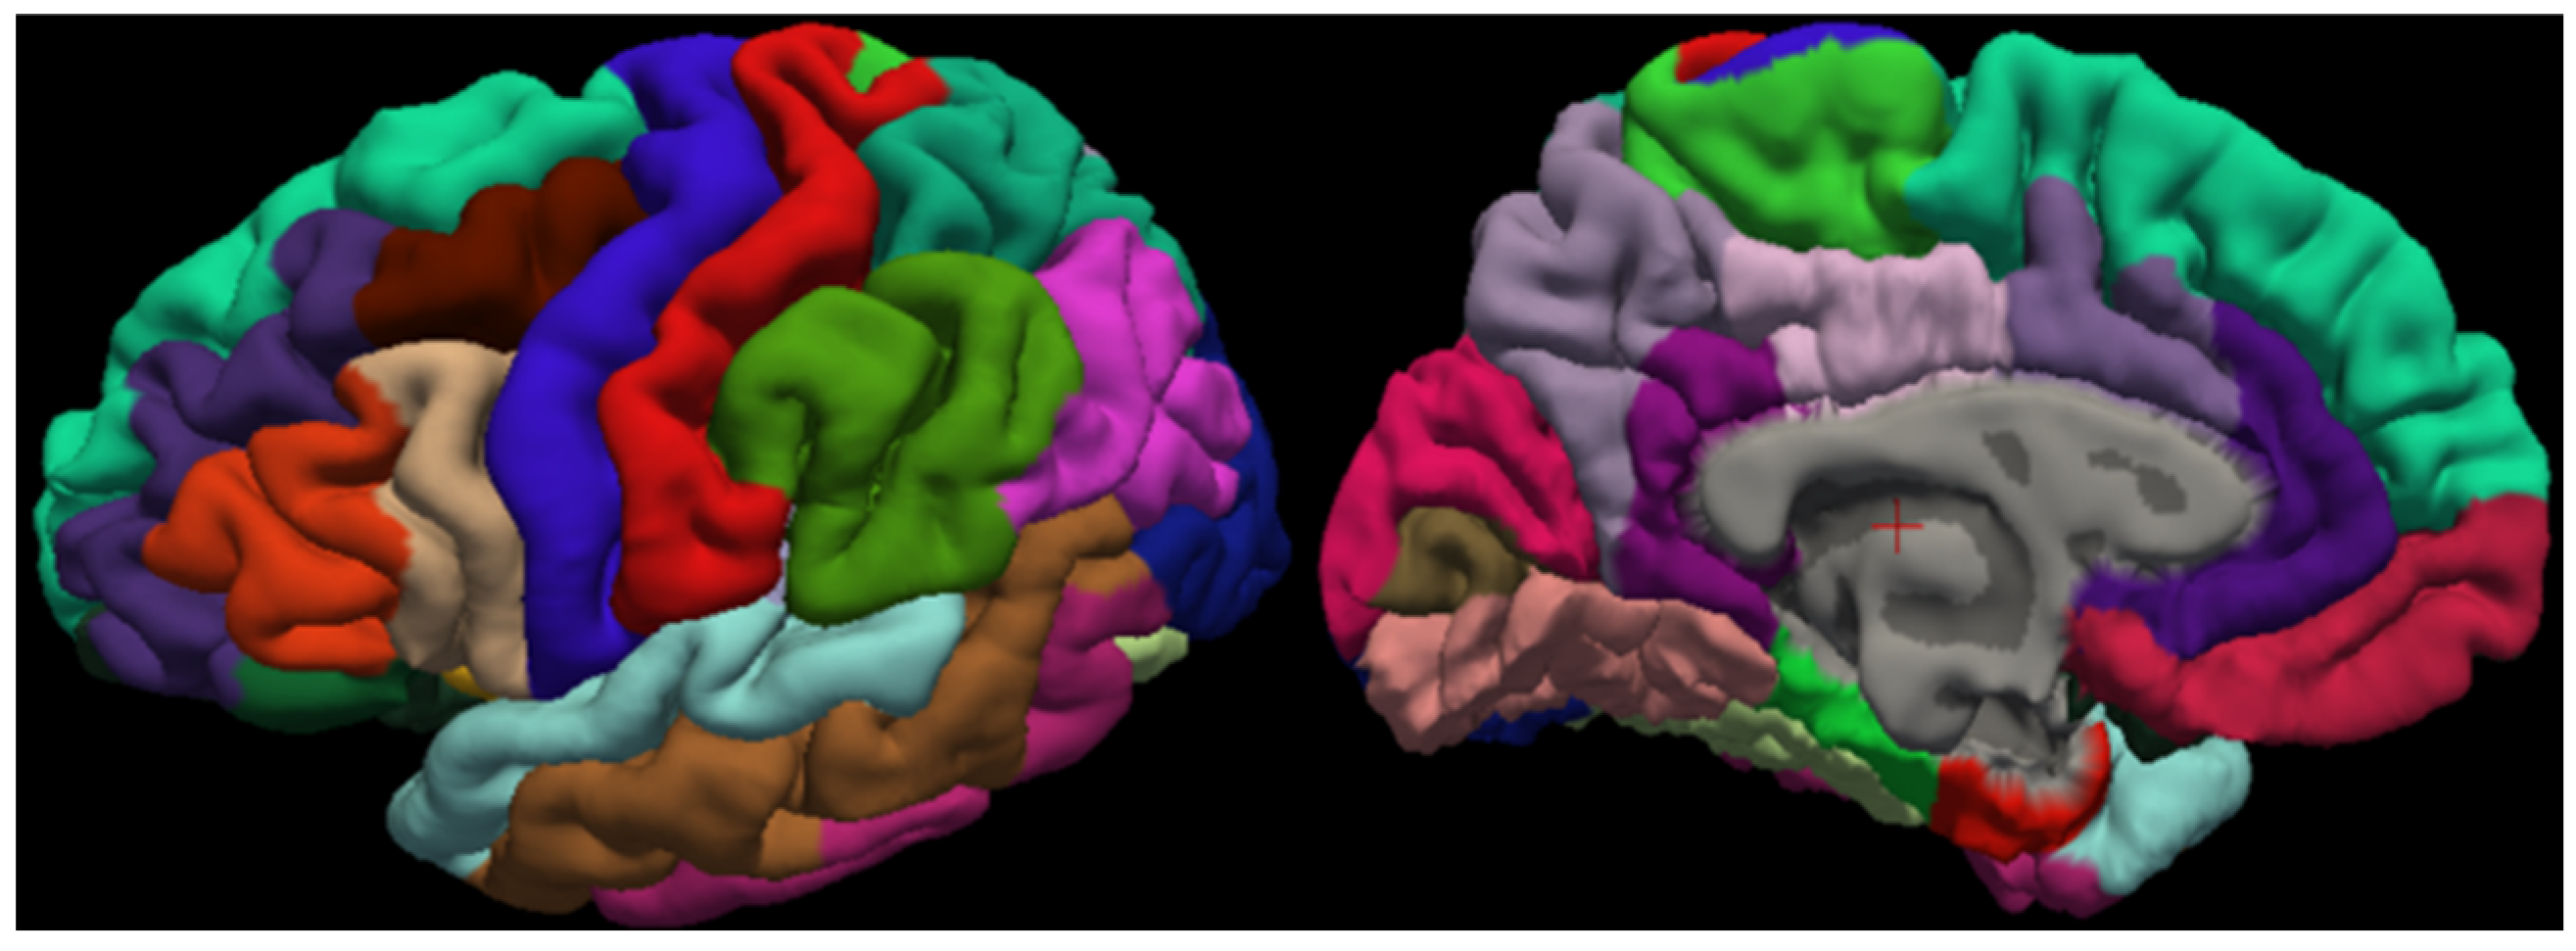

3.4. Cortical Structure Segmentation Results